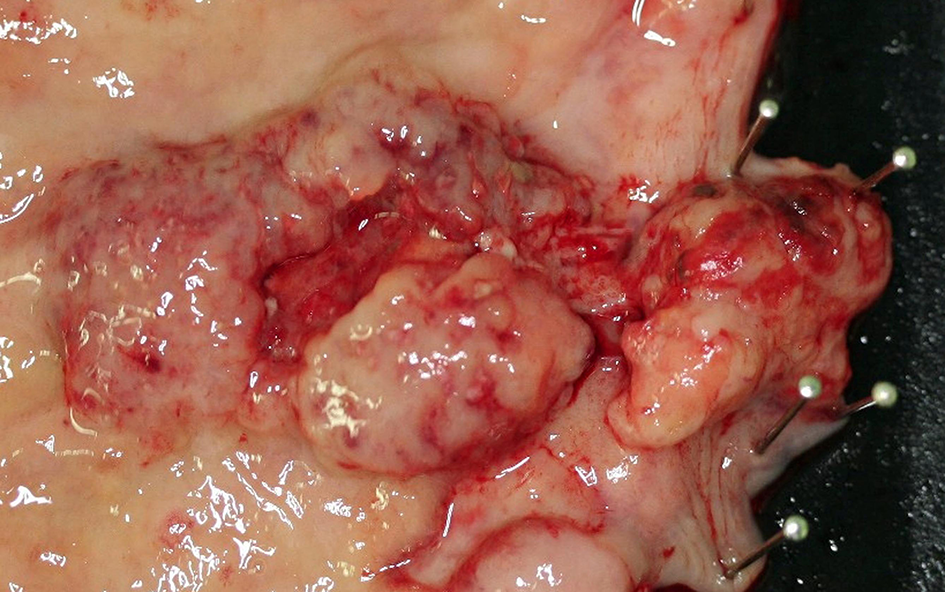

Figure 2

Neuroendocrine carcinoma (NEC) at the esophagogastric junction: a large ulcerated mass.